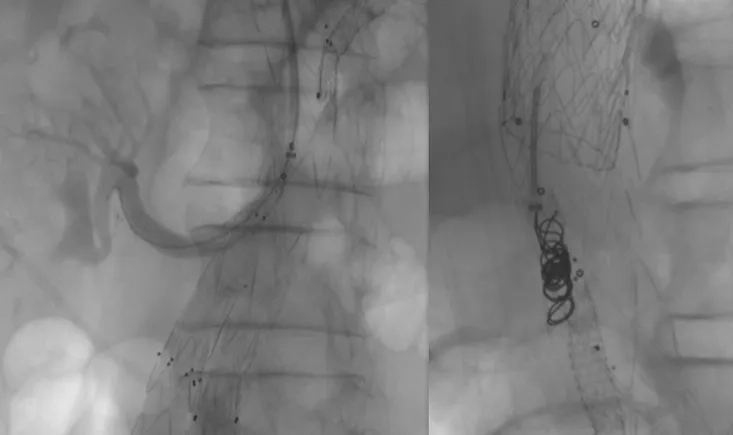

This case explores the management of a complex subclavian vein intra-stent occlusion in a haemodialysis pat…